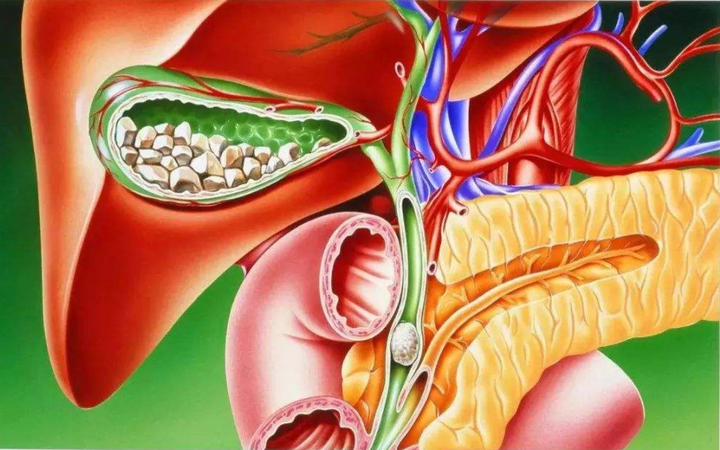

胆石は、胆嚢内に集まった物質(通常はコレステロール)が固まってできています。胆石は、胆管に痛みや炎症を引き起こすだけでなく、胆嚢を切除した場合でも胆管の閉塞を引き起こす可能性があります。

次に、これらの切り込みの 1 つからカテーテルを挿入し、胆嚢と総胆管を接続する胆嚢管にカテーテルを配置します。このカテーテルを使用して、特殊な種類の染料を管内に注入します。この色素を使用すると、外科医は胆嚢を切除して胆石の有無を確認しながら、モニターで胆管を観察できるようになります。

IOC が胆石があることを示した場合、外科医は手術中に胆石を除去するか、治療のための次回の予約をするよう指示することがあります。

医師は、胆管内に胆石が残っていないことを確認し、余分な胆汁を排出するために再診の予約を入れることもあります。